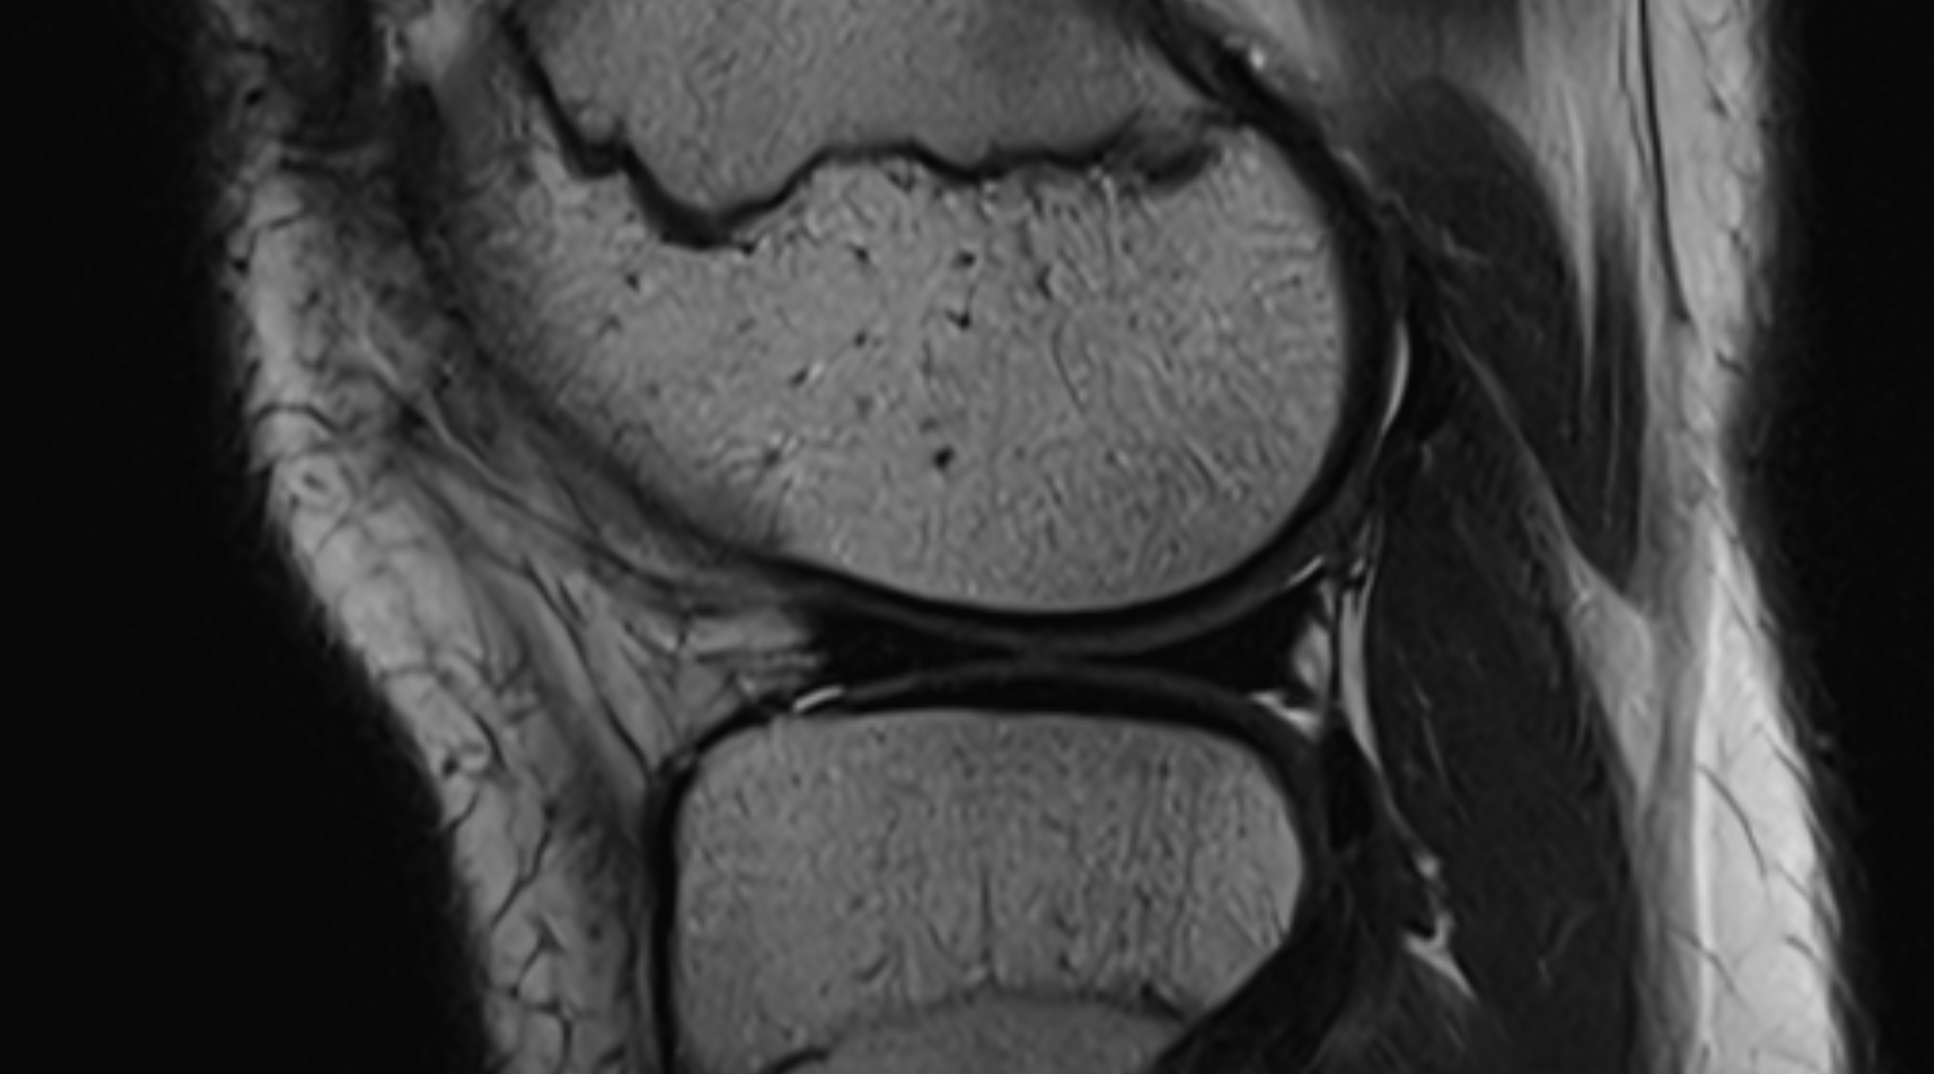

Condition Overview

A bucket-handle tear is a severe type of meniscal injury where a large vertical tear allows a strip of the meniscus (the "handle") to flip over and displace into the intercondylar notch of the knee.

This mechanical blockage frequently causes the knee to "lock" and prevents full extension, requiring surgical intervention to resolve.